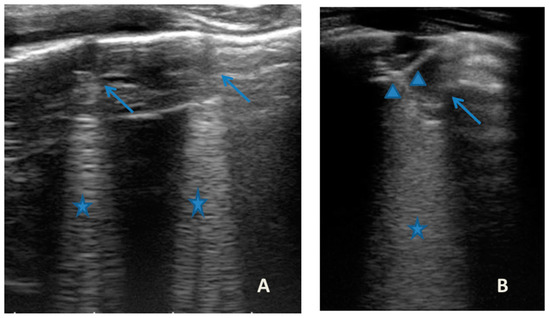

He came to our attention at the PED for acute onset of severe respiratory distress with diffuse bronchospasms and moderate-to-severe acute asthmatic attack: he presented severely dyspneic and tachypneic, unable to speak, he was tachycardic, and he had an oxygen saturation of 88–90% with consequent oxygen requirement. A chest X-ray was performed in the pediatric emergency room to rule out respiratory complications in consideration of the severity of the severe clinical picture. The radiographic picture (Figure 2) was interpreted as an inflammatory type consolidation. However, the child was apyretic, and the inflammation indices were negative, as were the molecular and culture microbiological tests of the airways for both viruses and bacteria.

Figure 2.

Chest radiography shows, on the left inferior lobe, non-specific areas of reduced transparency, associated with obliteration of the left lateral costophrenic sinus. It shows further subtle parenchymal hypodiaphania on the right mid-basal area.

In any case, therapy for acute asthma attack and antibiotic therapy was set up, and he was admitted to the pediatric ward. Here, at the same time as the clinical evaluation, we performed LUS, which showed the presence of a diffuse SIS, and three areas of lung atelectasis, one of which—present in the left posterolateral basal area—was associated with mild reactive effusion (Figure 3). The LUS picture was highly positive, but excluded the presence of inflammatory/infectious consolidations.

Figure 3.

Grayscale lung ultrasound examination shows: an irregular pleural line in all fields explored; on the left anterior-lateral field, mainly in the apical area; (A) and on the left anterior retrocardiac field, mainly in the mid-apical area; (B) consolidations of an atelectatic nature (arrow), associated with sonographic interstitial syndrome (SIS), represented by coalescent vertical artefacts or B-lines and “white lung” areas (asterisks); (C) on the left postero-lateral field in the basal area, consolidation of about 3 cm of atelectasis nature (arrow) with static air bronchograms (punctate) (arrowheads), associated with reactive transudative pleural effusion (white asterisk); (D) on the right lateral fields, diffuse sonographic interstitial syndrome (SIS), characterized by irregularities of the pleural line (white arrowheads) and long confluent vertical artifacts (asterisks).

On the basis of these data, the antibiotic therapy was therefore suspended, oxygen therapy was set at high flows in consideration of the presence of atelectasis, and the therapy of the moderate–severe acute attack was continued with subsequent suspension of respiratory support after about a week of therapy. Adequate preventive therapy [1,2,3] was also set up. The LUS follow-up showed complete resolution of the areas of atelectasis after 4 weeks from the start of preventive therapy, whereas long vertical artifacts and irregularities of the pleural line were still present.

In our cases (Table 1), particularly in the first three cases—children with asthma not controlled due to an inadequate preventive therapy for age, phenotype, and severity of the clinical picture [1,2]—LUS was highly positive (Figure 1, Figure 3 and Figure 5). It showed the presence of lung atelectasis, which resolved slowly after weeks of therapy of the acute attack and the beginning of adequate preventive therapy. On the contrary, in case 4 and 5—children with asthma well controlled by adequate preventive therapy—LUS was not highly positive (Figure 6 and Figure 7). In fact, it did not show large atelectasis, but a slight SIS in case 4, and a SIS suggestive of viral infection of the small airways in case 5 [14,15].